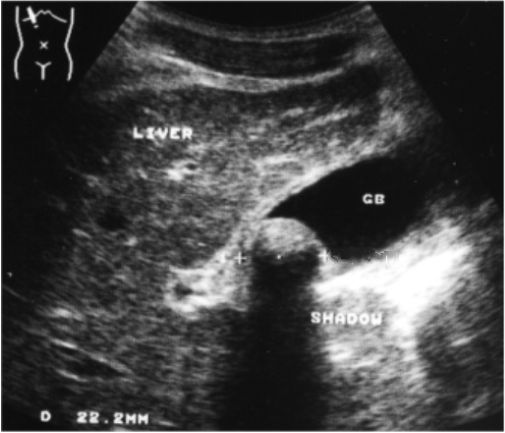

Examination of gallbladder revealed a large (2,2cm), echogenic, intraluminal mass with smooth surface. A broad acoustic shadow, posterior to the mass was present. Gallbladder wall was thin. Rest of the examination was normal.

Single gallstone in the gallbladder.